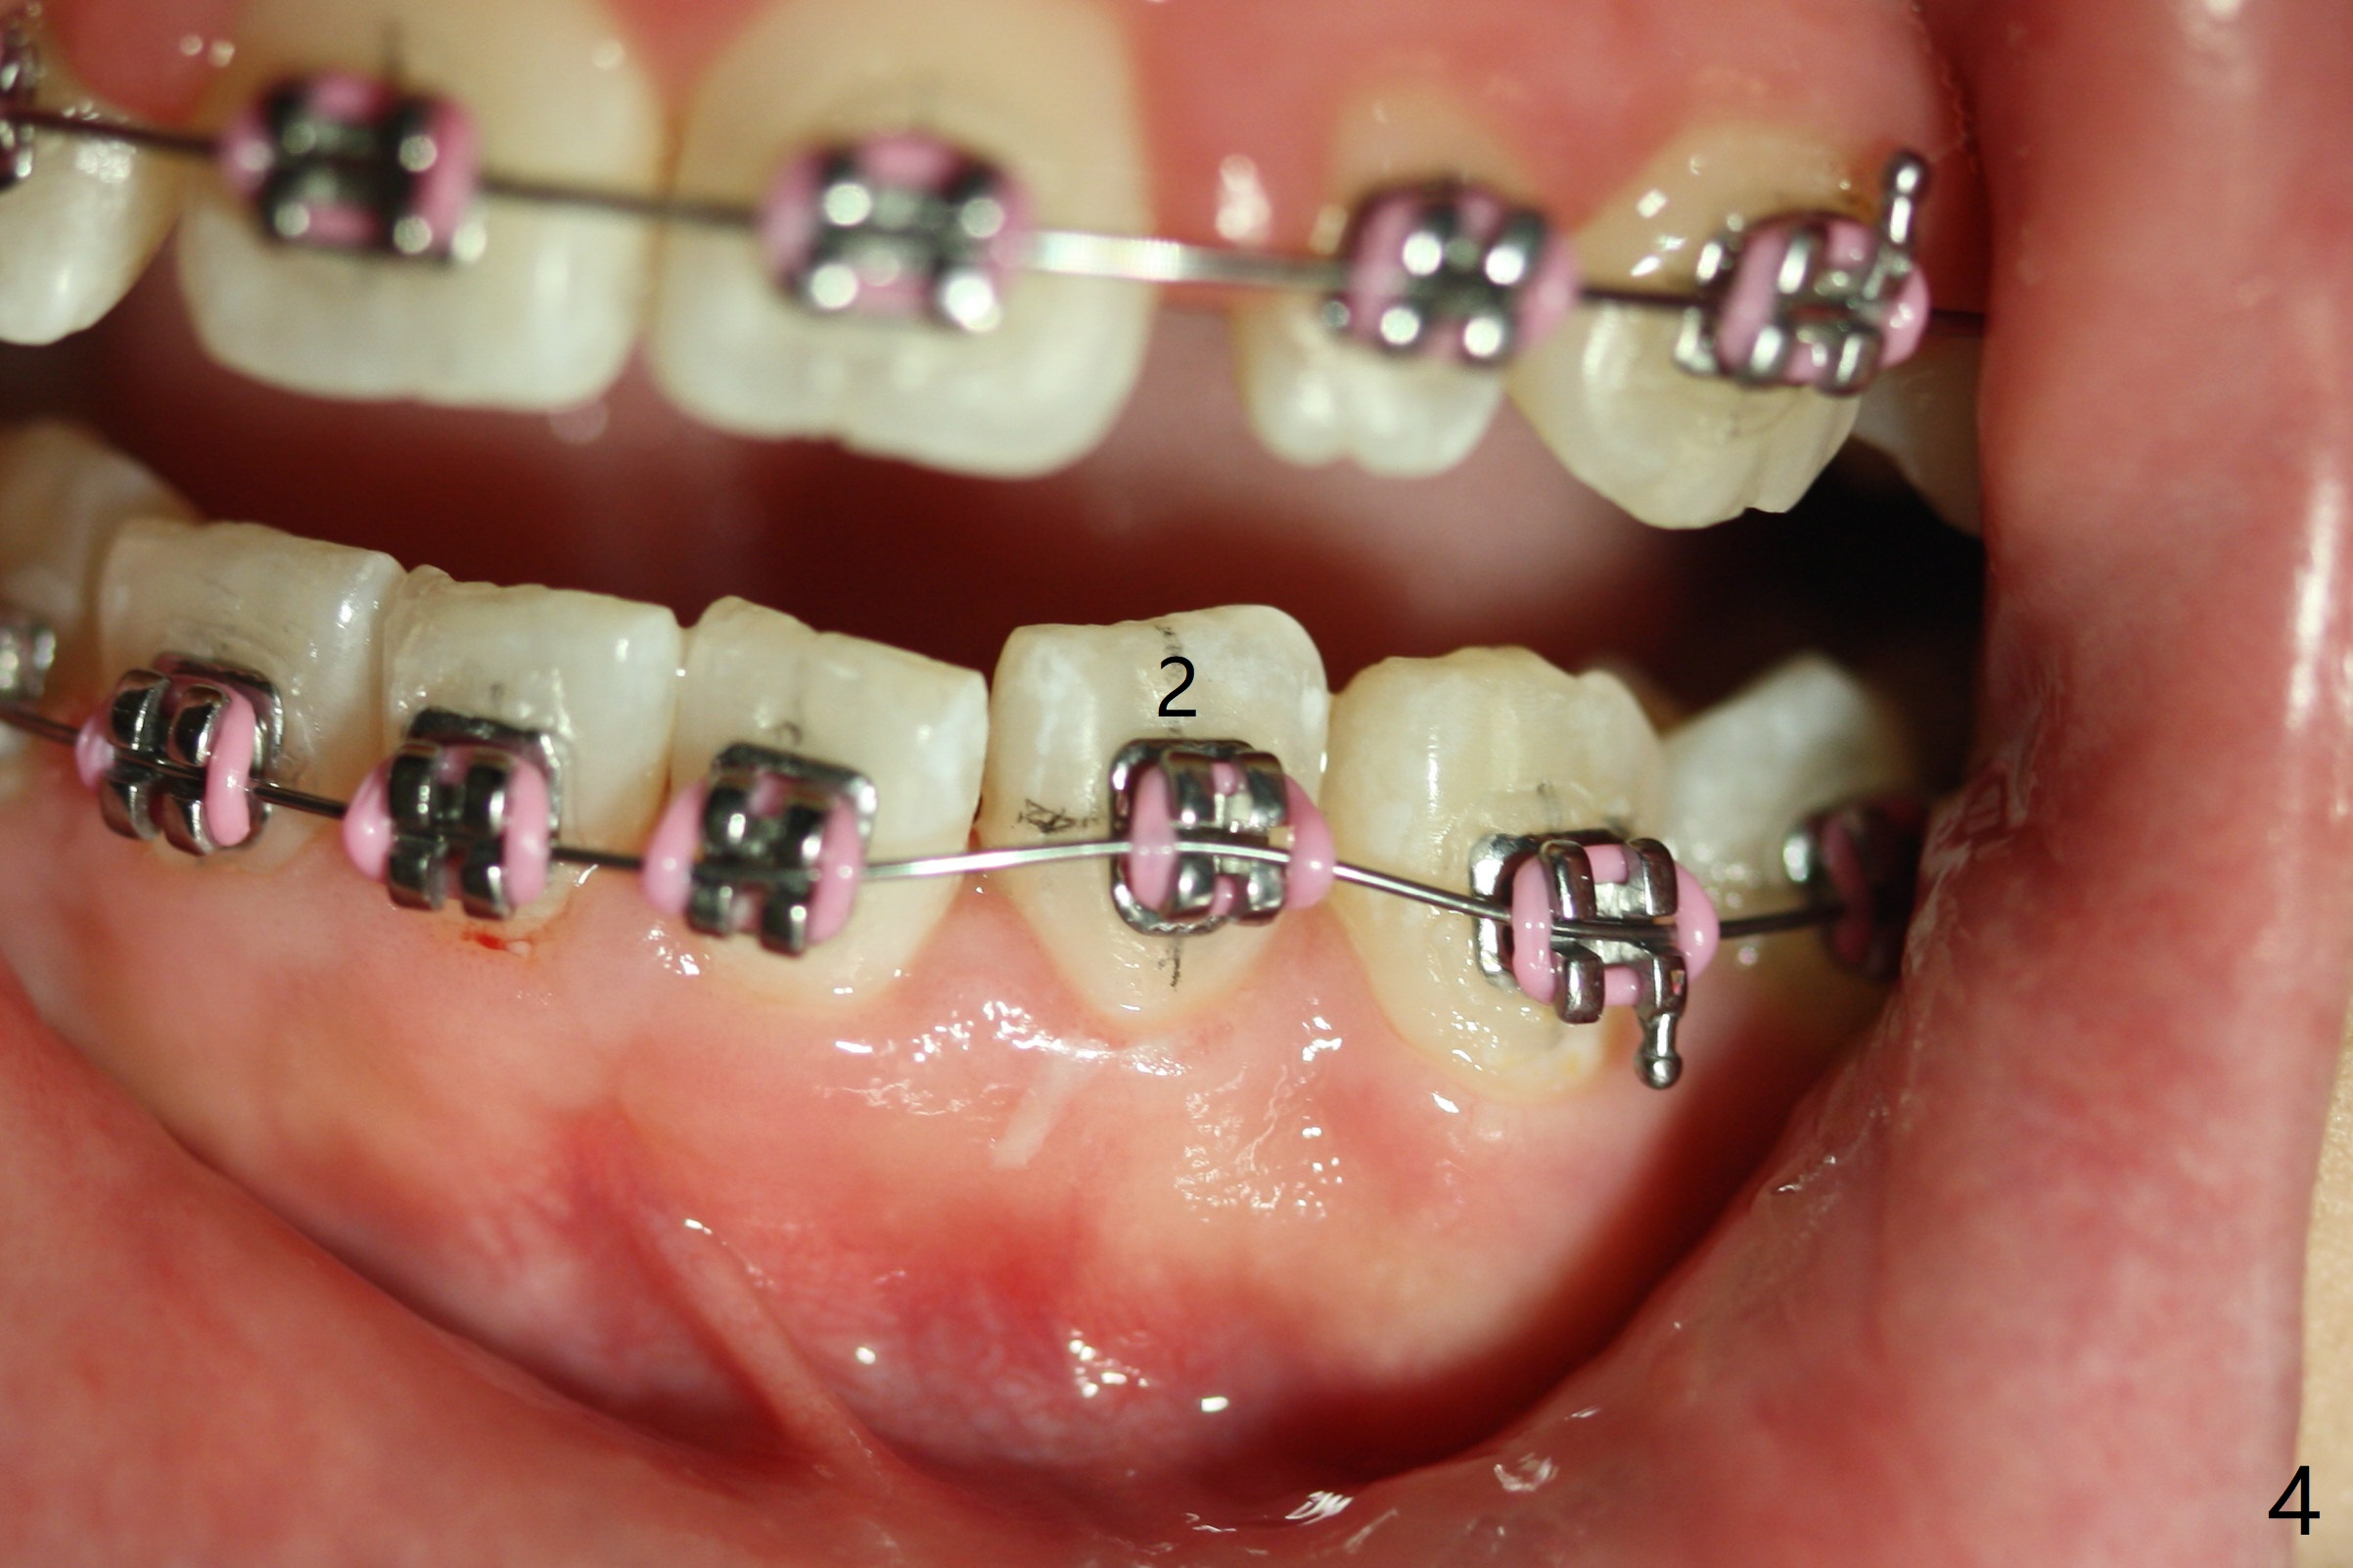

As planned, the peg laterals do not have brackets placed (Fig.2), since their position and shape will be ultimately decided by veneers. Alignment of the lower arch is more severe than that of the upper one, characterized by severe crowding at LR 3 and 4 (Fig.1) and rotation of LL 5 (Fig.3). Oral hygiene does not improve during orthodontic treatment. Impression will be taken prior to debanding. Space is obtained for LL2; brackets are placed at LL2 and 5; 14 niti wire is placed 9 months post banding (Fig.4-6). Orthodontic treatment is terminated prematurely partially due to poor oral hygiene.